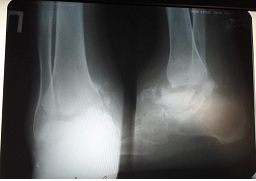

4. Рис.3а | |

| Тема | ||

| Тип | author.submit.suppFile.figureResearchMaterials | |

Посмотреть

(38KB)